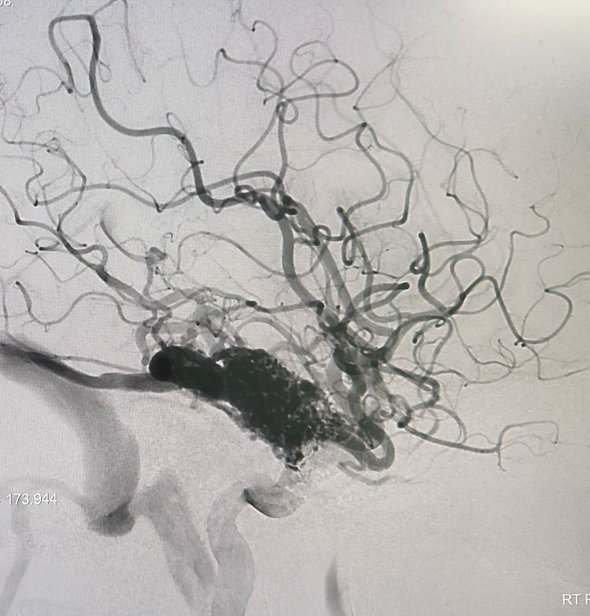

В больницу школьница экстренно поступила в остром состоянии. По словам медиков, проведенное обследование выявило кровоизлияние в мозг из-за лопнувшего сосуда и артериовенозную мальформацию сосудов головного мозга.

При данном виде патологии вены и артерии небольшого диаметра, переплетаясь друг с другом, образуют «сосудистый клубок», в котором произошел разрыв сосуда. Патология опасна тем, что может вызвать повреждение клеток мозга, нарушить их нормальную работу и при несвоевременном лечении привести к летальному исходу.

«Артериовенозная мальформация лечится методом эмболизации — введением в поврежденный сосуд специального вещества для заклеивания места разрыва. Нейрохирурги выполнили процедуру тонким катетером с ювелирной точностью. Операция длилась три часа и позволила „заклеить“ кровоточащий сосуд, снизив риск повторных кровотечений», — рассказал завотделением рентгенэндоваскулярной диагностики и лечения медучреждения Михаил Комиссаров.

фото: vk.com/roshal_kids